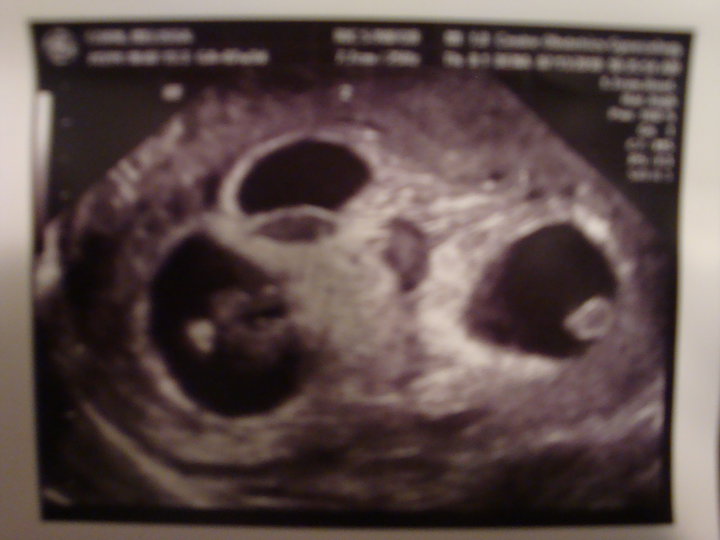

Ever seen an ultrasound like this?

For those not in the world of Facebook (Melissa posted this on Facebook last night), this is what an ultrasound of fraternal triplets looks like at 7.5 weeks. It is a picture of the ultrasound print-out that they gave us, so it's not extremely clear, but you can clearly see the three separate placentas. Pretty cool huh?

• Identical or fraternal? Our triplets are fraternal. Even very early on, we can confirm this on the ultrasound because each of the fetuses are clearly in their own sacs (placentas).